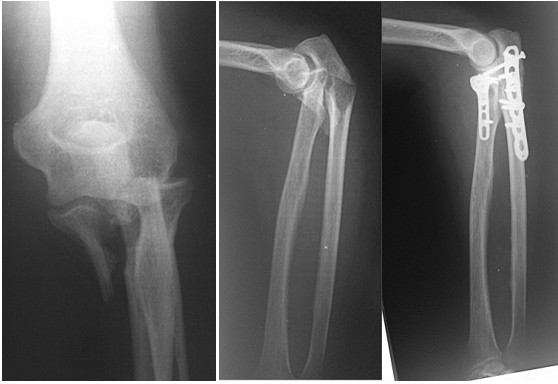

Реконструкция костей верхней трети предплечья пластинами